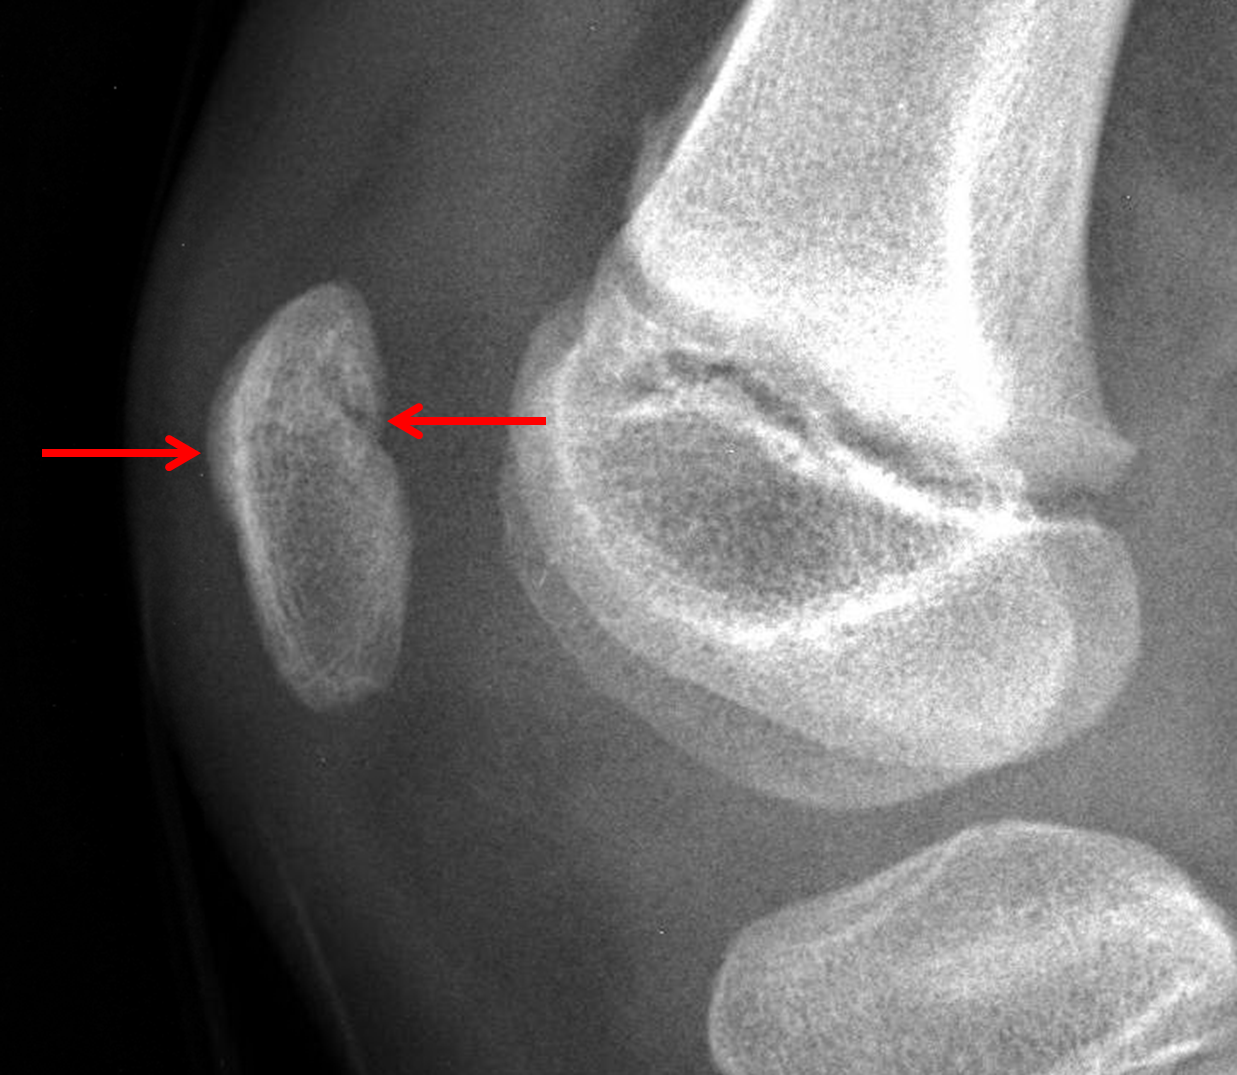

Age: 7

Sex: Male

Indication: Knee injury

Sample ReportAcute nondisplaced transverse patellar fracture with overlying soft tissue swelling.

Moderate-sized knee joint effusion.

No joint malalignment.